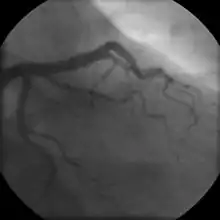

Coronary angiogram of a male

The diagnosis of CAD depends largely on the nature of the symptoms and imaging. The first investigation when CAD is suspected is an electrocardiogram (ECG/EKG), both for stable angina and acute coronary syndrome. An X-ray of the chest, blood tests and resting echocardiography may be performed.[73][74]

For stable symptomatic patients, several non-invasive tests can diagnose CAD depending on pre-assessment of the risk profile. Noninvasive imaging options include; Computed tomography angiography (CTA) (anatomical imaging, best test in patients with low-risk profile to "rule out" the disease), positron emission tomography (PET), single-photon emission computed tomography (SPECT)/nuclear stress test/myocardial scintigraphy and stress echocardiography (the three latter can be summarized as functional noninvasive methods and are typically better to "rule in"). Exercise ECG or stress test is inferior to non-invasive imaging methods due to the risk of false negative and false positive test results. The use of non-invasive imaging is not recommended on individuals who are exhibiting no symptoms and are otherwise at low risk for developing coronary disease.[75][76] Invasive testing with coronary angiography (ICA) can be used when non-invasive testing is inconclusive or show a high event risk.[74]